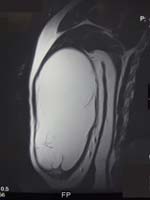

See Figures 3 and 4 below. Figure 3 illustrates the appearance of a soft tissue mass on MRI. This “fatty mass” in light color is a lipoma. Figure 4 illustrates the appearance of a sarcoma (cancerous growth) in the back of a person’s thigh. Click the image to enlarge